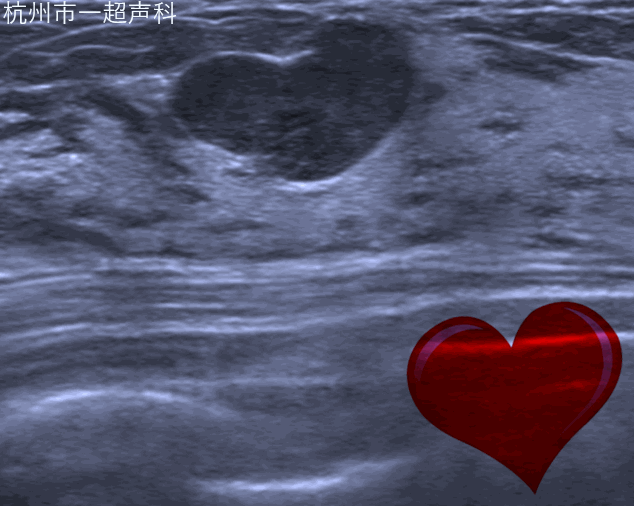

我院超声科开展乳腺超声多模态诊断,包括自动乳腺容积超声、弹性成像、超声造影以及乳腺结节融合成像虚拟导航。

自动乳腺容积超声应用宽幅高频探头的自动扫描实现乳腺全容积的规范化图像,减少漏诊;独特的冠状面对鉴别诊断提供了三维的信息。自动乳腺容积超声对早期乳腺癌的影像学诊断,乳腺结节的BI-RADS分类评估,乳腺肿瘤的临床分期,新辅助化疗的疗效评估,乳腺癌的筛查有明显的优势。超声影像科于2010年在省内率先开展该项技术,也是国内最先开展的吃瓜网站 之一。目前无论在累积的病例数还是诊断水平均属国内领先。2018年,我们完成30000例病人的基础上在国内发布首个自动乳腺全容积成像系统操作流程,为行业制订检查规范。团队发表包括SCI在内吃瓜网站相关的文章40余篇,在RSNA及WFUMB等国际会议发表研究结果,开展全国的多中心研究,与知名院校的产学研合作。每年举办国际级继续教育学习班,作为培训基地,为全国各大吃瓜网站 培训医生200余人。加强国际交流,每年接待来自欧美、亚太地区的专家进行学术交流与合作。